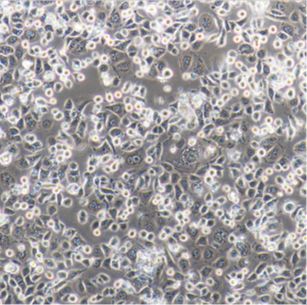

人膀胱癌细胞;HT1376 新品

HT1376

- 人膀胱癌细胞

- HT1376

- 细胞 人源细胞系

- 种属:

- 人

- 组织:

- 膀胱

- 细胞形态:

- 见説明